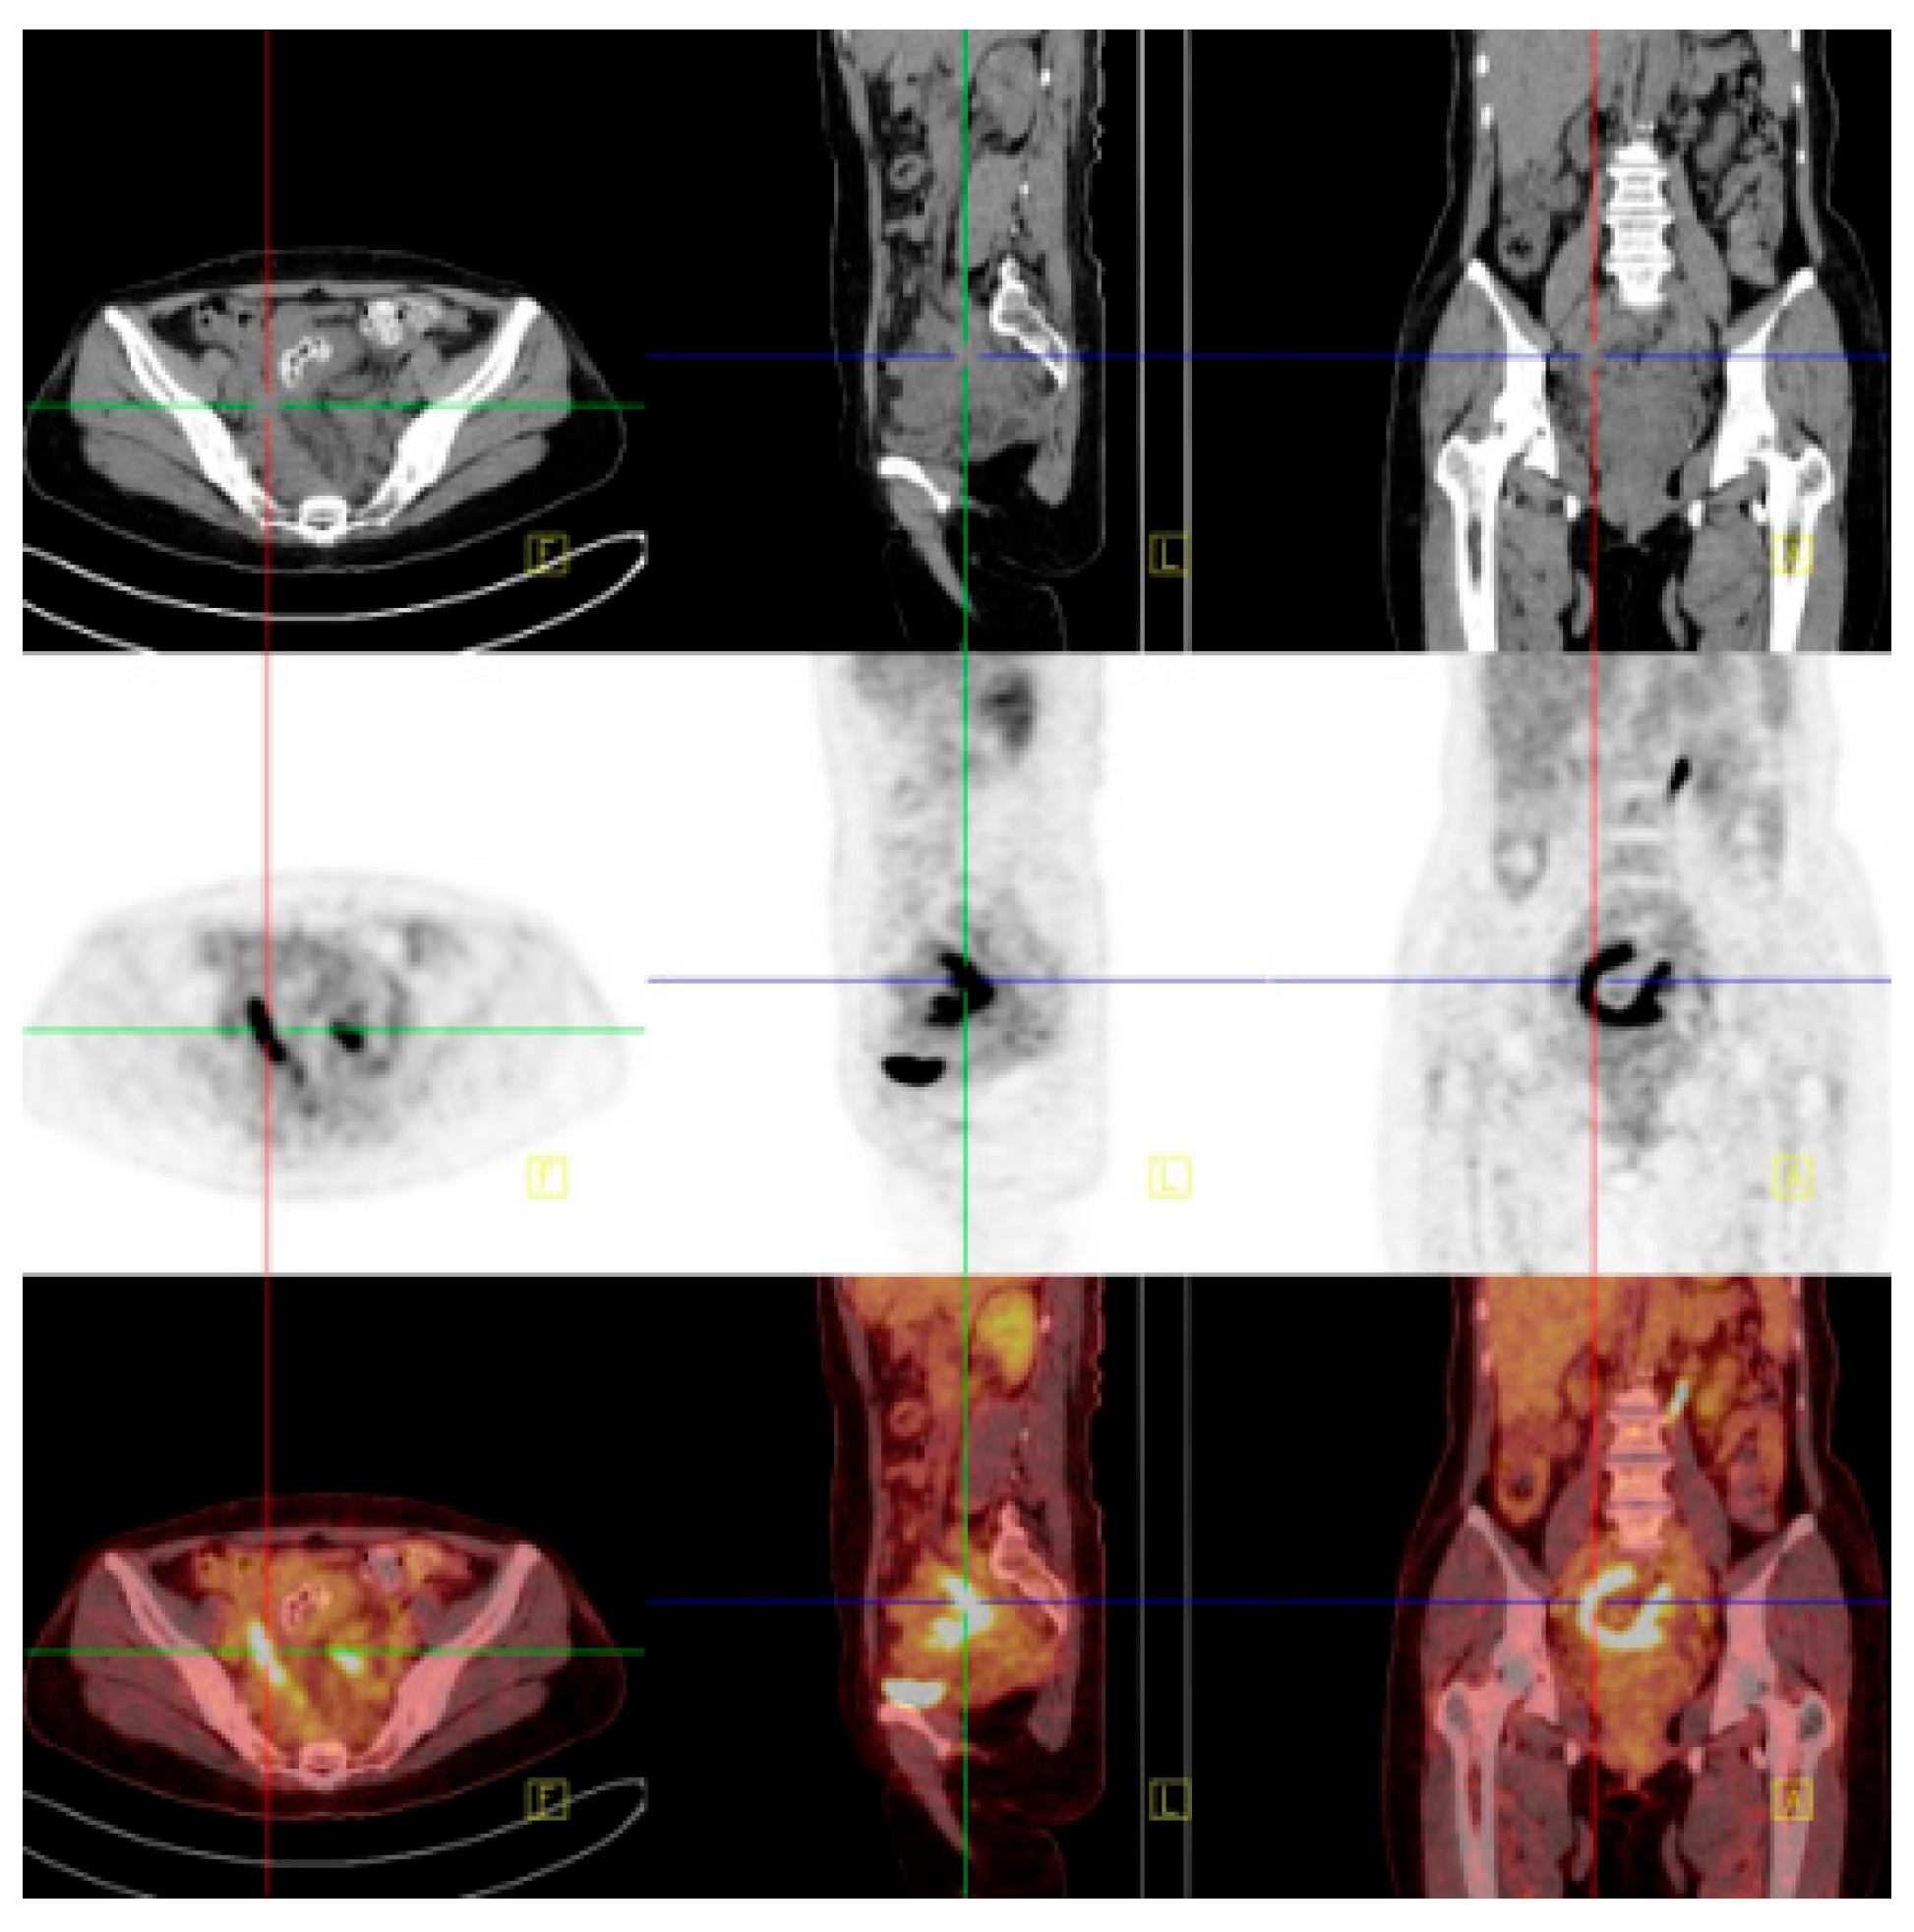

Figure 2.

Positron emission tomography–computed tomography (PET-CT) reveals an irregular high-density mass in the pelvic mesentery, forming a ‘C’ shape enveloping the sigmoid colon from the right, with unclear demarcation from the sigmoid colon and markedly increased FDG uptake. FDG can be used as an important indicator to distinguish benign and malignant lesions by reflecting the level of glucose metabolism in the lesion, but it does not have absolute specificity. Tuberculosis and inflammatory lesions can also show increased FDG. There may be chronic granulation tissue hyperplasia near actinomycete abscesses or sinuses, and the infiltration of various inflammatory cells, tissue cells, and fibroblasts, resulting in high uptake of 18F-FDG.

Figure 2.

Positron emission tomography–computed tomography (PET-CT) reveals an irregular high-density mass in the pelvic mesentery, forming a ‘C’ shape enveloping the sigmoid colon from the right, with unclear demarcation from the sigmoid colon and markedly increased FDG uptake. FDG can be used as an important indicator to distinguish benign and malignant lesions by reflecting the level of glucose metabolism in the lesion, but it does not have absolute specificity. Tuberculosis and inflammatory lesions can also show increased FDG. There may be chronic granulation tissue hyperplasia near actinomycete abscesses or sinuses, and the infiltration of various inflammatory cells, tissue cells, and fibroblasts, resulting in high uptake of 18F-FDG.